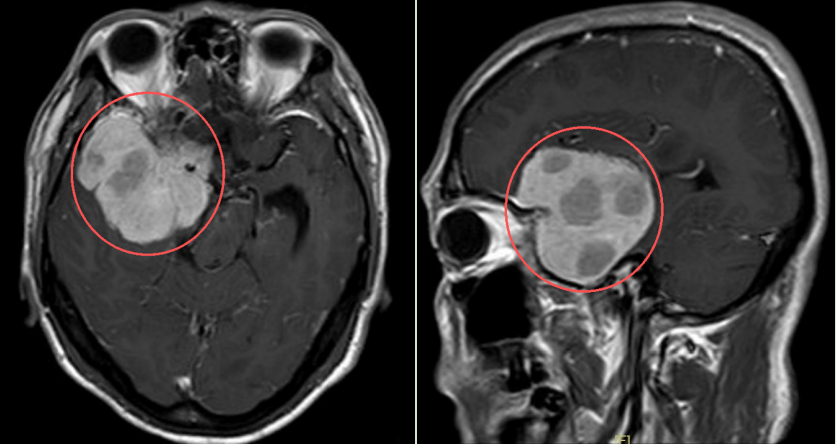

然而,从2025年10月起,他在跑步途中频繁在转弯处摔倒,偶尔还感觉一侧手脚乏力,起初并未放在心上。但随着摔跤次数不断增多,又无明显诱因地出现持续一周的头痛,他和家人终于警觉起来。同年11月中旬陈叔家人带他在当地医院做了一次检查,结果出来,医生发现他右额颞部蝶骨嵴占位病变,大小约5.5x6.6x5.8厘米,是考虑脑膜瘤。

该院神经外科彭彪主任、姚谦明教授等迅速牵头组织多学科会诊(MDT)。鉴于肿瘤体积巨大、位置较深,考虑为右侧额颞蝶骨嵴内侧型巨大脑膜瘤,肿瘤突入垂体窝和斜坡,环绕颈内动脉及分支、视神经等重要结构,压迫脑干,并且陈叔已经出现肢体乏力、视力受损、视物重影等进行性神经功能缺损症状,手术的难度和风险极高。但如果不及时干预,肿瘤可能进一步压迫脑组织,可导致陈叔出现偏瘫、失明甚至危及生命,到底该怎么办?

手术在高倍显微镜下进行,该院神经外科主任彭彪带领团队精准判断肿瘤边界,操作如“绣花”般细致,一分一毫谨慎分离,尤如在刀尖上行走,既要避免损伤视神经导致视力丧失,又要保护颈内动脉及其分支,在控制出血的同时确保大脑整体血供稳定。经过近8个小时的精细操作,肿瘤被完整切除,重要神经血管结构完好保留。术后,陈叔恢复良好,很快顺利出院。医生鼓励他积极康复,后续或有望重回马拉松赛场。